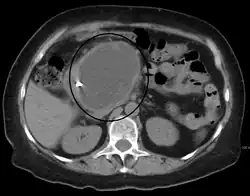

A pancreatic pseudocyst as seen on CT

A pancreatic pseudocyst is a circumscribed collection of fluid rich in pancreatic enzymes, blood, and non-necrotic tissue, typically located in the lesser sac of the abdomen. Pancreatic pseudocysts are usually complications of pancreatitis,[5] although in children they frequently occur following abdominal trauma. Pancreatic pseudocysts account for approximately 75% of all pancreatic masses.[6]